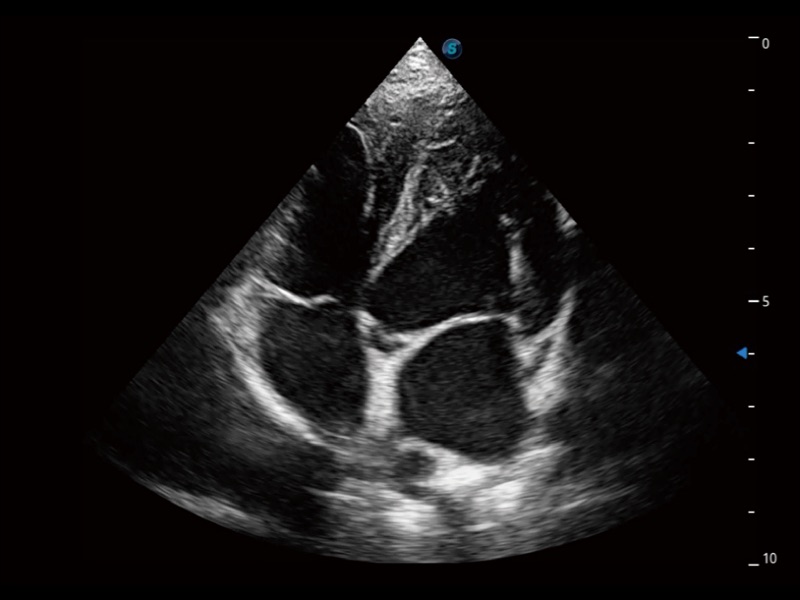

通过360度任意调节3条M型取样线,在同一心动周期上观察心脏不同位置的运动曲线,得到准确的心功能测量数据,有效评估心肌运动及左心室功能。

实时用颜色表示心肌组织运动,观察和定量组织的运动情况,对快速检测与评估心肌的灌注和活性、电传导及心肌收缩和舒张功能等均能提供重要的诊断信息。